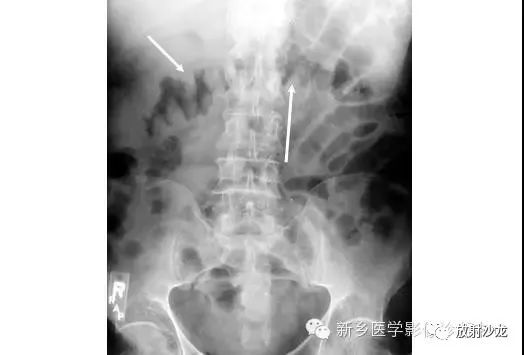

急性腹痛、便血的65岁男子行腹部平片检查所上图示。除了近端小肠梗阻,箭头指向有没有其它重大异常?

箭头指向缺血性结肠炎患者的拇指纹。拇指纹是粘膜水肿的非特异性的表现,其可见于炎性肠病、伪膜性结肠炎或缺血性肠病。随着水肿加重,结肠袋可能完全消失,留下一个管状的外观。肠道的收缩狭窄可能是其它常见的发现。